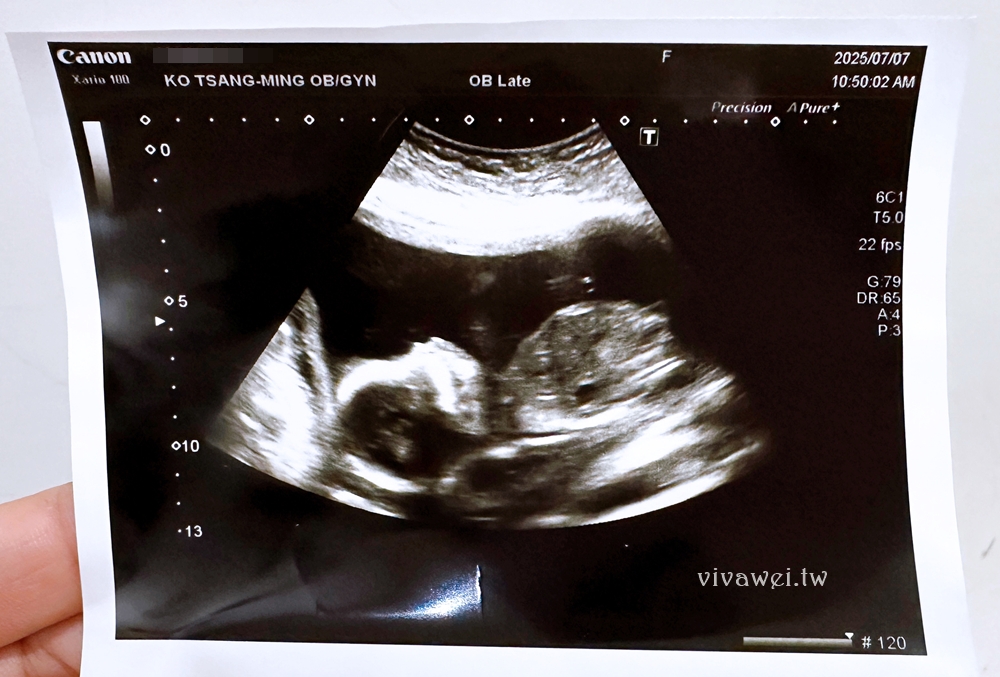

▲當日是由一位柯藥師進行問診,會問近期產檢有沒有遇到什麼狀況,有沒有出血的問題,也會簡單說明羊膜穿刺和羊水晶片檢查的內容項目!接著會安排到超音波室由護理人員協助照超音波,會在照超音波的時候確認性別、寶寶的心跳、羊水量等!

▲照完超音波以後,柯醫師很快就出現,護理人員會先幫我的肚子上碘酒,醫師戴上手套以後,先用超音波照肚子,然後很快地細針就插下去了(全程都可以拍照和錄影)!

這是我第二次抽羊水,覺得這次抽的酸痛感比較明顯,但都還在可以忍受的範圍,過程護理人員會希望我可以看著螢幕,但我實在是直接閉眼睛不想看,想要趕快結束這一回合啊!

▲全程大約不到3分鐘就抽完兩管羊水,速度很快,動作很俐落,抽完以後在外面休息五分鐘就可以離開,等待兩週後的報告結果!